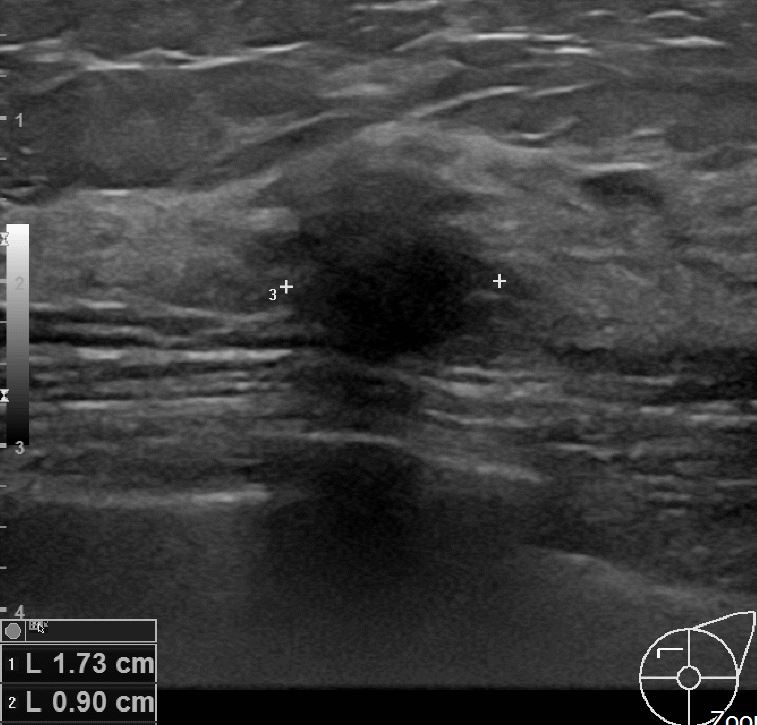

상기환자 외부검사상 이상소견으로 내원하신 50대 여성분으로 초음파 검사 후 좌측유방 의심스러운혹 조직검사 시행한 후 유방암진단 되었습니다.